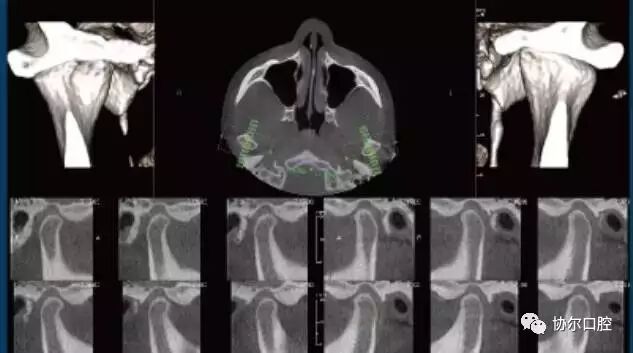

口腔锥形束CT

Quantum iQ的专利图像处理技术提供平滑的软组织影像,并最大程度的显示硬组织和骨结构的细节及对比。

最全面的诊疗解决方案

完整的骨结构TMJ分析

强大的3D正畸分析

精确的气道分析

一句话,使用KaVo 3D eXam i独有的软件可以准确而高效地实现对种植、基台、修复体的设计,帮助种植、修复、牙体牙髓以及正畸计划的制定和实施。完整的骨结构TMJ分析,精确的气道分析是很多三合一CBCT达不到的,也是医生在诊断中容易忽视的。工欲善其事,必先利其器,好的影像学检查资料,将为医生的治疗锦上添花。